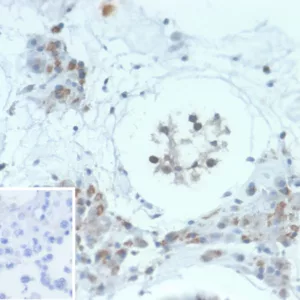

Immunohistochemistry (IHC)

1-2ug/ml

30 min at RT. Staining of formalin-fixed tissues requires heating tissue sections in 10mM Tris with 1mM EDTA, pH 9.0, for 45 min at 95°C followed by cooling at RT for 20 minutes

Recognizes a protein of kDa, which is identified as HGAL. It contains a putative PDZ-interacting domain, an immunoreceptor tyrosine-based activation motif (ITAM), and two putative SH2 binding sites. In B cells, its expression is specifically induced by interleukin-4. HGAL is specifically expressed in germinal center B-cells, but is absent in mantle and marginal zone B-cells and in the inter-follicular and para-cortical regions in normal tonsils and lymph nodes. Its high degree of specificity for germinal center B-cells makes anti-HGAL an ideal marker for the detection of germinal center-derived B-cell lymphomas. HGAL expression has been used to help elucidate nodal marginal zone lymphoma (NMZL) from cases of diffuse follicle center lymphoma. Additionally, HGAL expression was shown to correlate with survival in patients with diffuse large B-cell lymphoma (DLBCL).

Daudi, Raji or U266 cells. Human lymphocytes. Human lymph node, tonsil or testis.